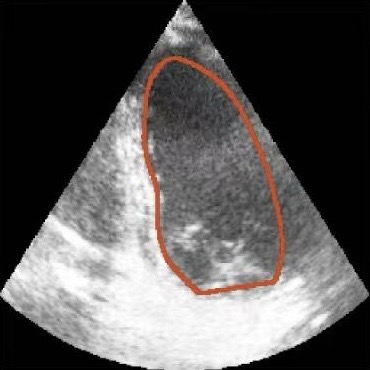

Challenges in Echocardiography Segmentation 超声心动图视频分割面临的挑战

Echocardiography segmentation faces several challenges such as low contrast, speckle noise, and signal dropout. 超声心动图视频分割面临着诸如低对比度、斑点噪声和信号丢失等多重挑战。

Shape

(c)

Scale

(d)

Cycle

(e)

Dropout

(f)

Figure 2. Illustrative challenges for echocardiography video segmentation: (a) speckle noise, (b) indistinct or blurred contours, and (c-f) the substantial changes in the target’s shape and scale throughout the cardiac cycle. 图 2. 超声心动图视频分割面临的典型挑战:(a) 斑点噪声,(b) 轮廓不清或模糊,以及 (c-f) 在整个心动周期中目标的形状和尺度发生的显著变化。